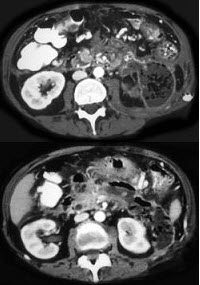

患者,女,57岁,上腹部隐痛半年余,CT片,最可能的诊断是( )

A:胰腺癌

B:胰腺脓肿

C:胰腺假性囊肿

D:胰腺囊腺瘤

E:胰岛细胞瘤